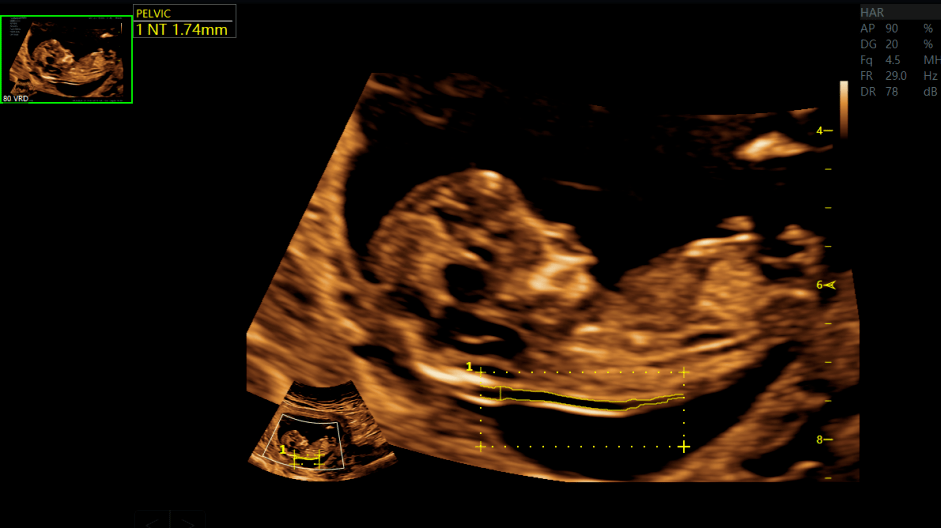

nt颈项透明层厚度自动测量为了准确测定孕期,医生还会测量胎儿的头臀

图片尺寸941x528